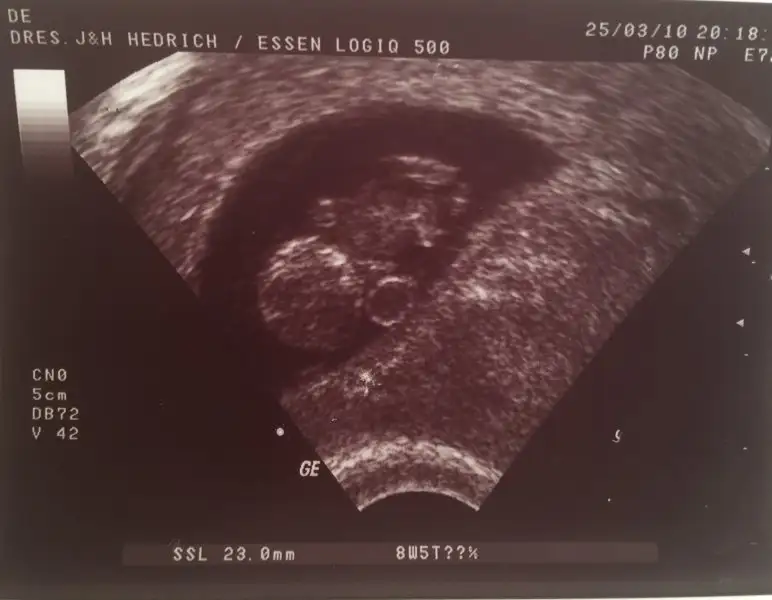

İlk hamileliğimdeki ultrason resimlerine bakıyordum buraya da eklemek istedim belki merak eden olur kaçıncı haftada nasıl görünüyor diye

Bu da 8 hafta 5 günlük

IMG_2988.webp